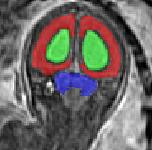

Limiting failures of machine learning systems is of paramount importance for safety-critical applications. In order to improve the robustness of machine learning systems, Distributionally Robust Optimization (DRO) has been proposed as a generalization of Empirical Risk Minimization (ERM). However, its use in deep learning has been severely restricted due to the relative inefficiency of the optimizers available for DRO in comparison to the wide-spread variants of Stochastic Gradient Descent (SGD) optimizers for ERM. We propose SGD with hardness weighted sampling, a principled and efficient optimization method for DRO in machine learning that is particularly suited in the context of deep learning. Similar to a hard example mining strategy in practice, the proposed algorithm is straightforward to implement and computationally as efficient as SGD-based optimizers used for deep learning, requiring minimal overhead computation. In contrast to typical ad hoc hard mining approaches, we prove the convergence of our DRO algorithm for over-parameterized deep learning networks with ReLU activation and a finite number of layers and parameters. Our experiments on fetal brain 3D MRI segmentation and brain tumor segmentation in MRI demonstrate the feasibility and the usefulness of our approach. Using our hardness weighted sampling for training a state-of-the-art deep learning pipeline leads to improved robustness to anatomical variabilities in automatic fetal brain 3D MRI segmentation using deep learning and to improved robustness to the image protocol variations in brain tumor segmentation. Our code is available at https://github.com/LucasFidon/HardnessWeightedSampler.